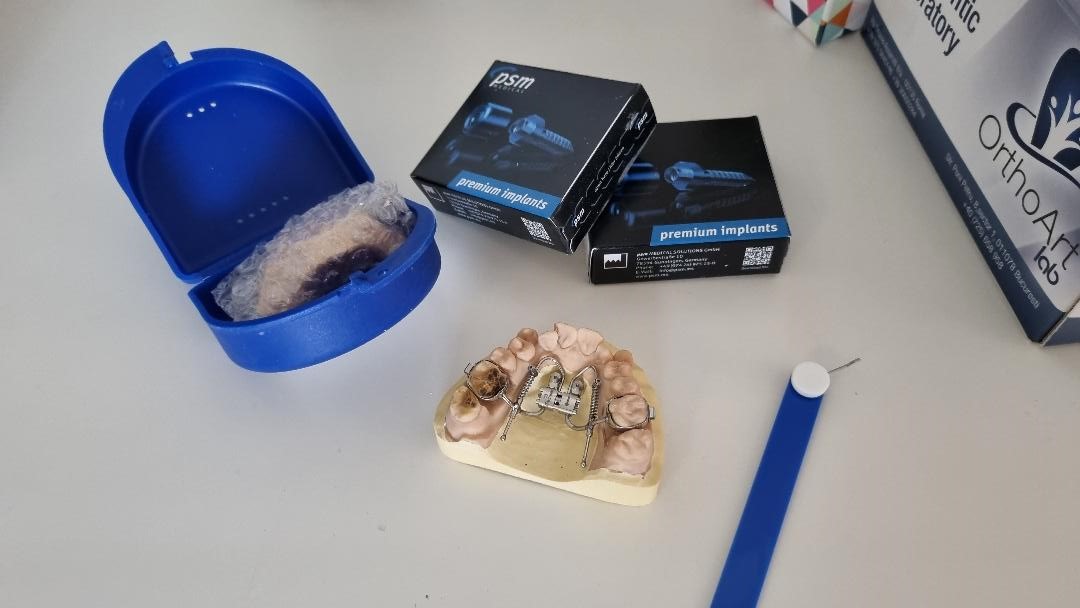

Disjunctoare hibride

Disjunctor ancorat pe miniimplanturi.

Este utilizat in cazurile nechirurgicale si non-extractionale pentru marirea maxilarului superior.

Mini implanturile

Sunt mici surburi confectionate din titan ce ofera un punct de sprijin la nivelul osului.

Acestea pot fi pozitionate in diverse locuri in functie de necesitate, cel mai des fiind introduse intre radacinile dentare.

Aplicarea acestor elemente ortodontice se face sub anestezie locala, fiind introduse cu usurinta la nivelul osului maxilar.

Miniimplanturile pot fi folosite atat a intruda dintii care au migrat in sens vertical cat si pentru a-i readuce in pozitie corecta pe cei care au migrat orizontal(basculat), dar si in unele sitatii ce necesita inchiderea spatiilor.